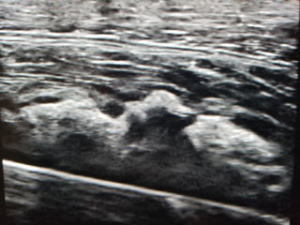

写真:アキレス腱断裂 超音波画像 最大底屈して断裂部(GAP)が十分寄るかどうかチェックしています。